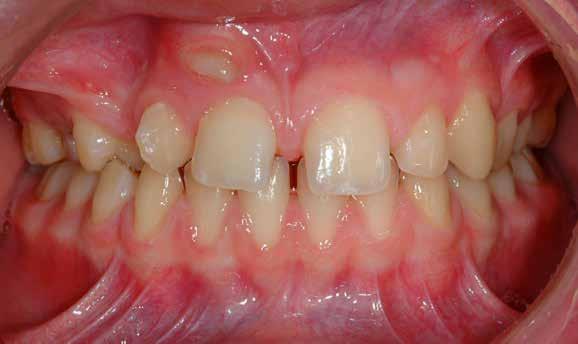

Lány páciensem I. fázisú kezelését 10 évesen kezdtük el bimaxilláris funkciós, kivehető készülékkel. Megfigyelhetőek a class 2-es eltérésnél tipikusan jellemző szűk felső és alsó fo-

gívek, valamint a nagy overjet, a mandibula disztál helyzete, továbbá a felső metszőfogak protrúziója, amelynek kialakulásához sokszor hozzájárul az ujjszopás is (1-3. képek)

A vegyes fogazati kezelési célok a fogívek tágítása és a mandibula meziális irányú növekedésének a biztosítása volt. Fontos, hogy az ilyen típusú készülékeket nem csak éjszaka, hanem napközben is – amennyit csak lehet – hordani kell a minél hatékonyabb működés érdekében. A 18 hónapos első fázisú kezelésnek köszönhetően az alap kezelési célok megvalósultak, sikerült a class 1-es okklúziót beállítani (4-7. képek).